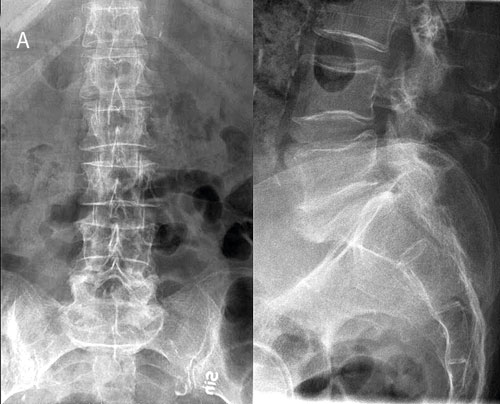

Figur 1. En 59-årig man, opererad och strålbehandlad 4 år tidigare för halstumör (röd flagga!) sökte på grund av värk i höger klinka ut mot höftleden. Han behandlades med antiflogistika och sjukgymnastik utan effekt. Vilovärk och sömnsvårigheter (röd flagga!) tillkom; B-SR 42 mm. Röntgen ländrygg, bäcken och höger höftled (A) visade degenerativa förändringar med fasettledsartros i nedre ländryggen men inga maligna förändringar. Besvären fortsatte och patienten sjukskrevs; 3,5 månader efter första remissen utfördes MRT ländrygg och bäcken. Denna visade på koronal STIR-sekvens en stor högsignalerande tumör som fyllde ut foramen ischiadicum majus på höger sida (B, pilar) samt en meta­stas i vänster os ilium (B, pilhuvud). På T1-viktade sekvenser sågs lågsignalerande metastaser i L4 och L5 (C, pilar) samt i sakrum (D, pil).